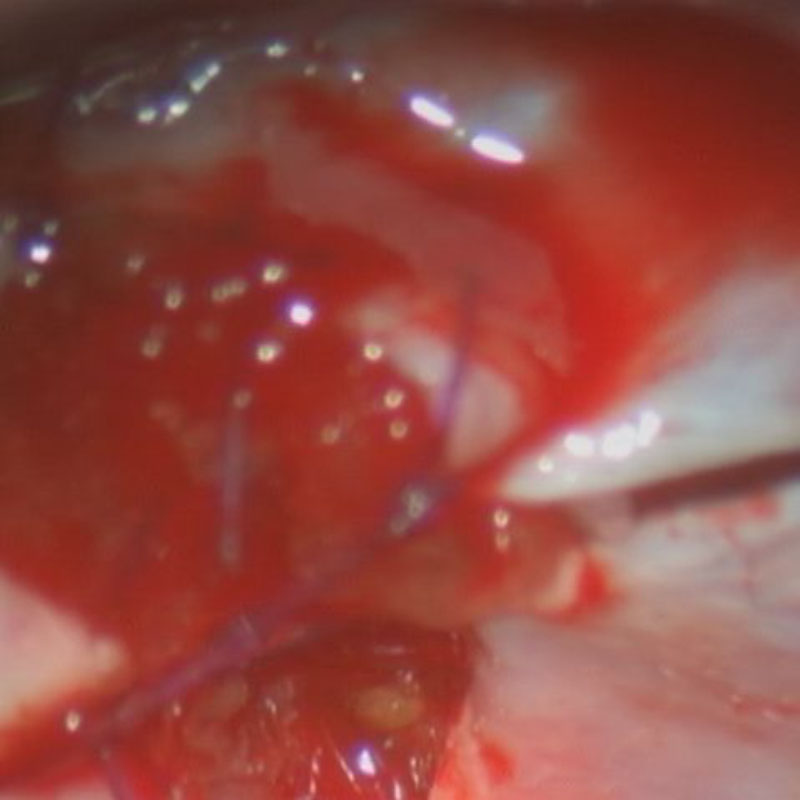

術中写真

摘出 中